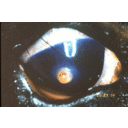

Squamous cell carcinoma, corneoconjunctiva.png